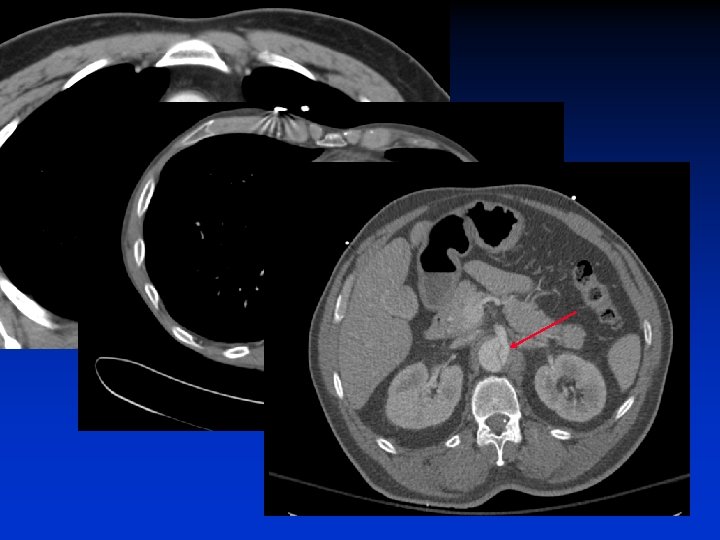

Acute Type B and Malperfusion Mechanism § Dynamic – – § Pressurization of false lumen and mobile dissection flap Leads to narrowing or occlusion of true lumen Dynamic process Degree of malperfusion relates to degree of compression Compromised perfusion to end organ Static – Dissection extends into branch vessel – Narrows branch vessel – Creates a fixed obstruction § Combination Department of Surgery, University of Pennsylvania Health System

IVUS-Dynamic Compression Department of Surgery, University of Pennsylvania Health System